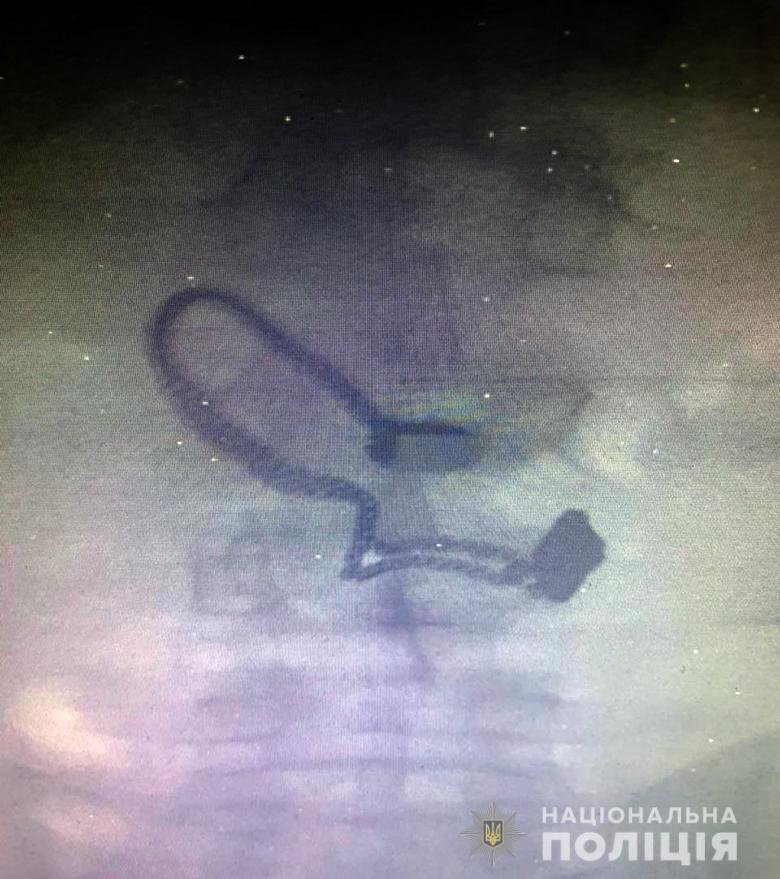

Приехавшие на место преступления правоохранители принялись поверхностно осматривать нарушителя и нашли у него кошелек потерпевшей, а вот цепочку - не нашли. Позже мужчина признался полицейским, что сорванную цепочку он проглотил. Во время медосмотра на рентген-снимке задержанного врачи увидели украшение.